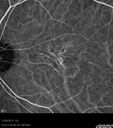

59-year-old man has macular dystrophy in both eyes. He saw Dr. Gass in 1989, at which time Dr. Gass thought it might be post inflammatory. Interestingly, at this point he still does not have a diagnosis other than macular dystrophy. His vision since he was here last is reasonably stable.

He has been diabetic for eight years. He had LASIK surgery done in 1998. He was a high myope, about a -10 and now he is about a -3. He had some vision changes in medical school in the 1980s and saw Dr. Gass for that. He had some pigment epithelial irregularities in both eyes. Dr. Gass felt maybe this was an atypical case of previous AMPPE. Otherwise he is in good health. He had strabismus as a child and had muscle surgery. He is color blind, along with many people in his family, and as far as he knows, it is congenital.

VISUAL ACUITY: Vision OD is 20/25, OS is 20/30. IOP: OD 14, OS 13. The lenses are clear.

OD: Vertical C/D ratio is 0.2. There are no vitreous cells. The retinal vessels are slightly attenuated. The retina is very thin looking.

OS: Vertical C/D ratio is 0.2. Again, the retinal vessels are attenuated. The retina does appear to be thin looking.

OCT SCAN: The OCT scan shows retinal atrophy in both eyes.

1. RETINAL ATROPHY – BOTH EYES

Non-specific (uncharaterized / unknown) Macular Dystrophy - ICG439 views59-year-old man has macular dystrophy in both eyes. He had some vision changes in medical school in the 1980s and saw Dr. Gass for that. He had some pigment epithelial irregularities in both eyes. He had strabismus as a child and had muscle surgery. He is color blind, along with many people in his family, and as far as he knows, it is congenital.

20/25, 20/30     (0 votes)